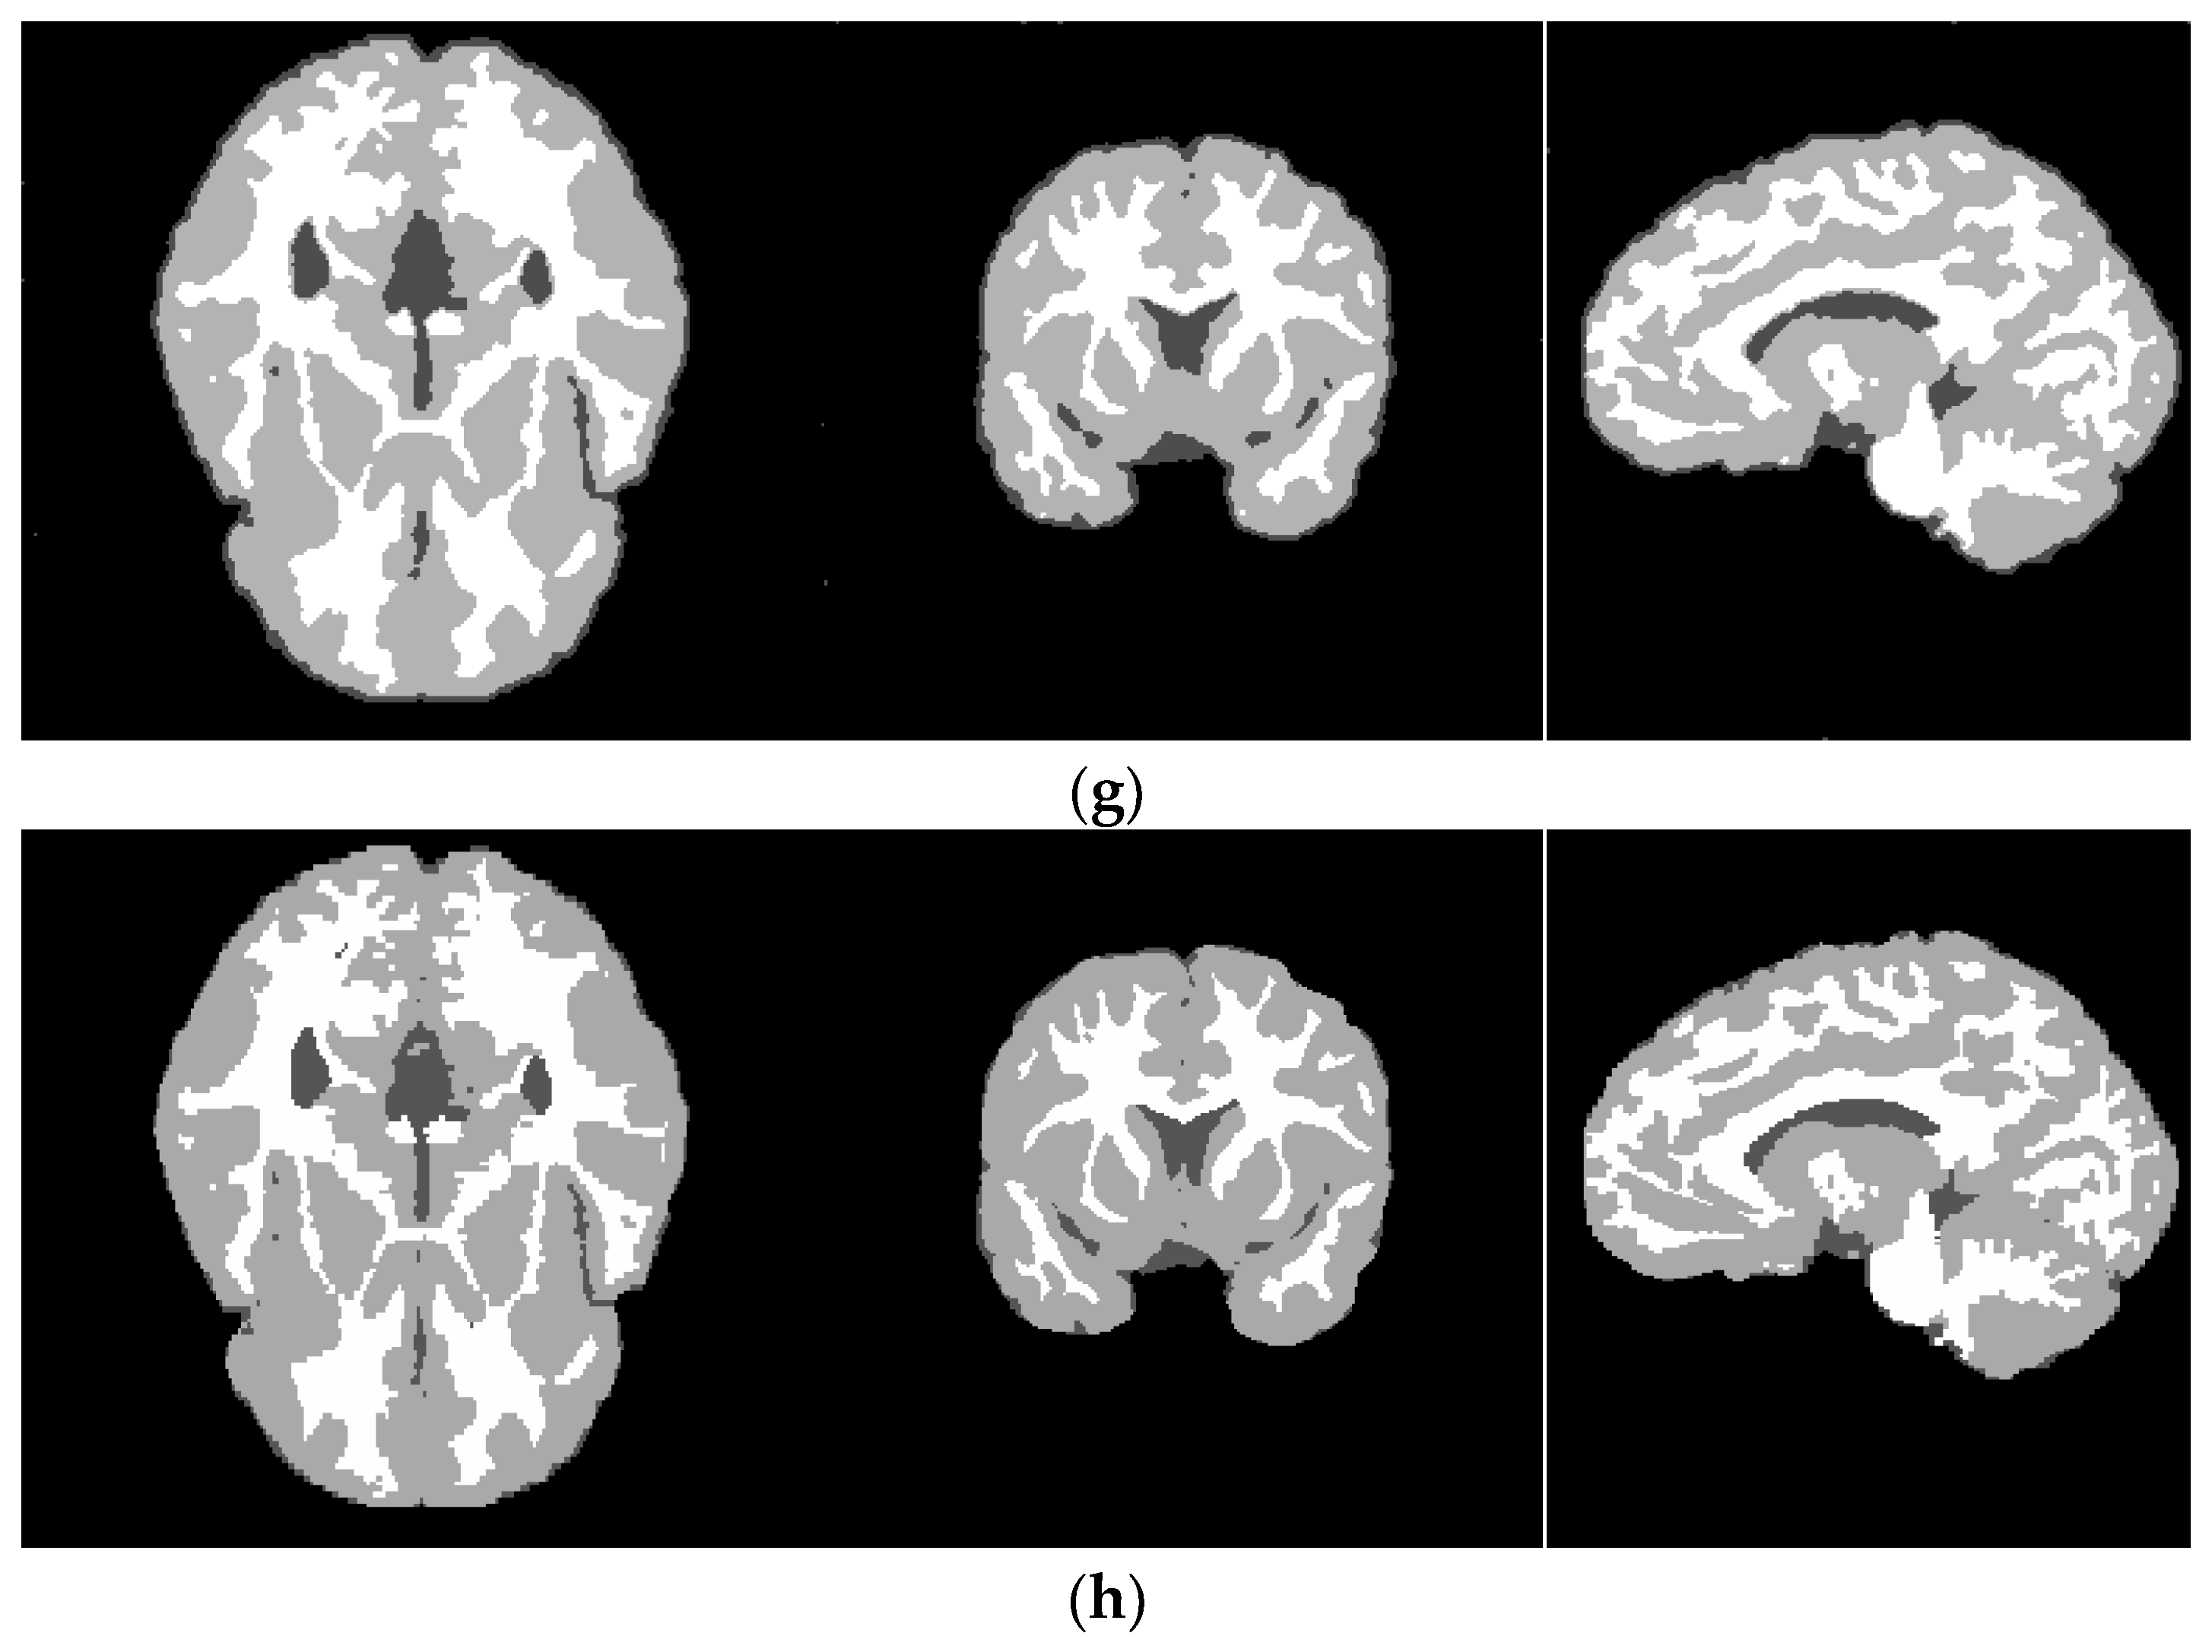

4.3. Real Brain MR Images